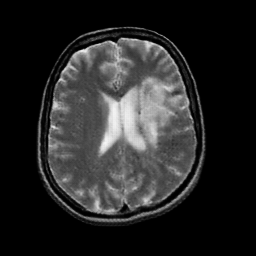

In this paper, we propose a bidirectional learning model, known as dual contrast cycleGAN (DC-cycleGAN), for medical image synthesis from unpaired data. Specifically, a dual contrast (DC) loss is formulated that leverages the advantage of samples from the source domain as negative samples to indirectly build constraints between real source and synthetic images via discriminators, and synthesize images more related to the target domain by enforcing the synthetic images to fall far away from the source domain. In addition, structural similarity index (SSIM) [35] and cross-entropy (CE) [48] are integrated into the DC-cycleGAN structure to avoid disappearing gradient information that is caused by a mean absolute error (MAE) and synthesizing irrelevant images. SSIM considers luminance [35] and CE converges fast as its back-propagation error is less than MSE [28]. As can be seen in Figs. 1 and 2, using SSIM and CE with dual contrast can generate more clear and accurate MR images as compared with that of MAE and MSE, and SSIM and CE without dual contrast loss. Although both SSIM and CE with dual contrast and without dual contrast generate similar CT images, SSIM and CE with dual contrast quantitatively generate better images as shown in Table 4. The experimental results indicate that DC-cycleGAN is able to consider more complex features such as structure in synthesizing images and produce remarkable results as compared with other state-of-the-art methods reported in the literature.

Tables 3 and 4 show the results of MR and CT synthesis, respectively. As can be seen, all components play vital role in both tables. SSIM & CE (w) performs significantly better than other losses in synthesizing MR images. This also can be seen visually in Fig. 1. In contrast, SSIM&CE (w) performs slightly better than SSIM&CE (wo) in synthesizing CT images, both generate more or less similar CT images (see Table 4).